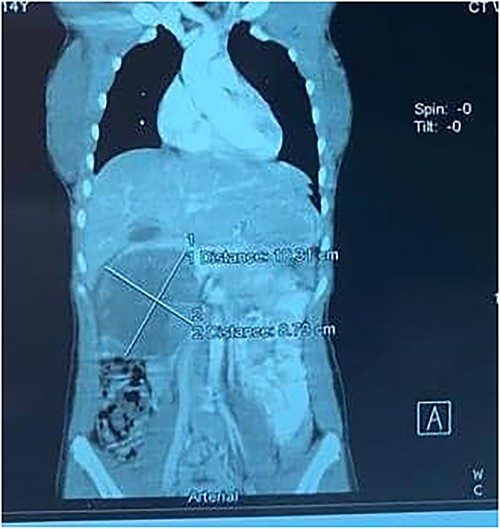

A 14-year-old female with no relevant past medical history presented with a 2-week history of right upper quadrant abdominal swelling. She gave no history of trauma, pain, fever, jaundice, alteration in bowel habits, early satiety, bloating, or anorexia. On physical examination, she appeared healthy. Her vital signs were normal, and she was anicteric. The rest of her exam was normal except for a right upper quadrant fullness and a palpable liver edge 6 cm below the right costal margin. An abdominal ultrasound was interpreted as a right lobe liver mass. A fine needle aspirate revealed necrotic tissue with no hepatocytes seen. A thoraco-abdominal CT scan revealed an enhancing, centrally necrotic retroperitoneal mass of 9 × 12 cm compressing the duodenum, portal vein, and inferior vena cava. Mild adjacent free fluid was noted. There was no evidence of metastatic disease (Fig. 1). All routine blood tests including complete blood count, chemistries (amylase and lipase inclusive) and coagulation studies were normal. A gastrointestinal stromal tumor was suspected.

A contrast-enhanced CT scans of the abdomen showing a large, well-defined, and heterogeneous tumor.